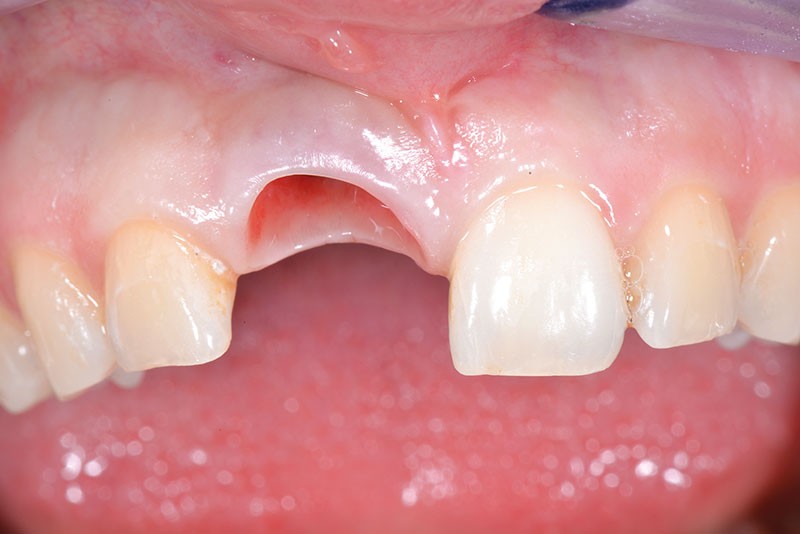

L’implant a été posé alors que la patiente était âgée de 17 ans (le 13 août 2004), à la suite d’un traumatisme entraînant la perte de cette dent (fig. 2a à d), puis la couronne a été posée 5 mois plus tard (le 7 janvier 2005).

Nous proposons de retirer la couronne et le pilier implantaire, d’effectuer une greffe de tissu conjonctif enfouie afin d’améliorer le volume du tissu kératinisé péri-implantaire [5] et de procéder à la pose d’une couronne provisoire transvissée (fig. 3a à h).